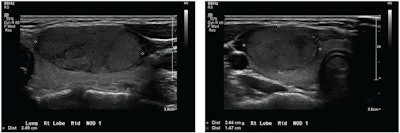

Longitudinal and transverse grayscale ultrasound images show a thyroid nodule in a 17-year-old patient with benign follicular adenoma, based on surgical excision alone. The overall impression for all three radiologists was benign (true negative). The ACR TI-RADS recommendation for all three radiologists was fine-needle aspiration (false positive). The deep-learning algorithm recommendation was also fine-needle aspiration (false positive). Images courtesy of ARRS.Three radiologists independently characterized nodules as benign or malignant based on overall impression and TI-RADS. The algorithm meanwhile determined the malignancy likelihood for each nodule, which was used to derive risk level. From there, each method was compared for sensitivity and specificity, with radiologist impressions having the advantage for specificity. However, TI-RADS and the algorithm showed higher sensitivity.